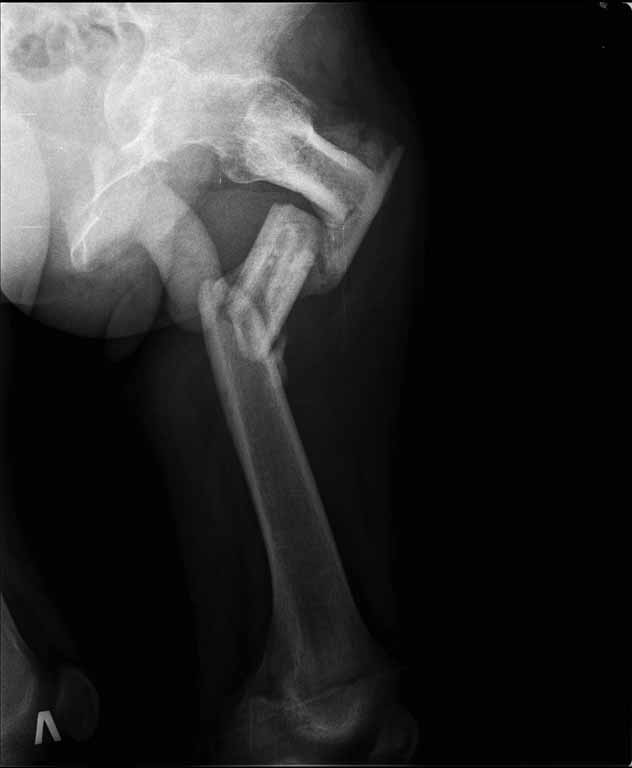

Пациенту 22 года. Травма в июле 2010г, лечился в районной больнице. К нам попал в апреле 2011г.Тяжелая сочетанная травма (29.07.2010): тупая травма живота с повреждением внутренних органов. Закрытая травма грудной клетки с переломом ребер. Пневмоторакс справа. Тяжёлая позвоночно-спинномозговая травма. Закрытый осложнённый переломо-вывих С5 позвонка. Верхний парапарез, нижняя параплегия, нарушение функции тазовых органов по типу недержания. Цекостома. Пролежень левой ягодичной области. Неправильно консолидированные переломы верхних третей обеих бедер. Застарелый вывих левого бедра.Осложнение: Поддиафрагамльный абсесс слева, забрюшинного пространства. Свищ желудка и ободочной кишки. Синегнойный сепсис. Двухстороняя пневмония. Но это уже анамнез.Пациент был неоднократно оперирован на органах брюшной полости и осложнениями с ними связанными.

В ягодичной области слева глубокий пролежень размером 2х2см, дном является вывихнутая головка бедра. Неврологически в нижних конечностях динамика положительная, появились движения в правой стопе, чувствительность в стопах.По переломам бедер: подвижности в местах переломов нет, снимки высылаю.

Планирую начать с правого бедра, ЧКО таза (передняя рама) с фиксацией бедра. О/клазия места перелома правого бедра и устранение грубых смещений в аппарате. окончательно можно оставить и в аппарате. Далее аппаратное устранение вывиха левого бедра.